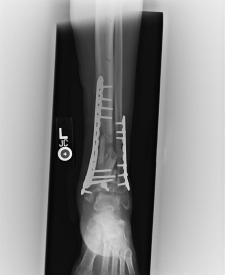

Post-corrective surgery X-Rays of the damaged right & left legs / ankles

The first two x-rays show Liam’s left ankle and pelvis prior to the accident. For comparison purposes it is interesting to see the

differences. The next x-rays were taken after the corrective surgery performed by Dr. Armendariz. Noticed that Dr. Armendariz has used tibia

bracing and also aligned the bone fragments of the left leg so that they could heal in the proper orientation. The external fixation has been

removed and Liam’s left foot has been returned to a more natural alignment.